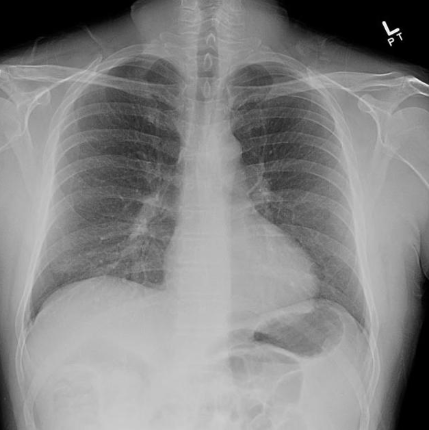

CXR findings Acute HP

Diffuse small 1-3mm nodules or infiltrates

GG

Apical sparing

Normal in 20%